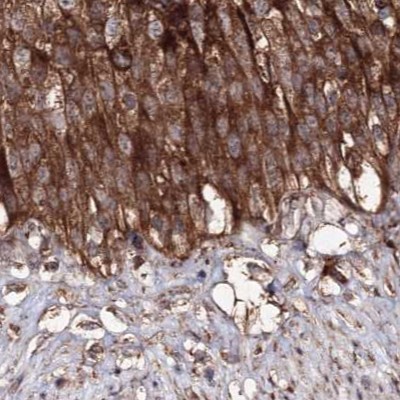

Immunohistochemical staining of human cerebral cortex, colon, lymph node and urinary bladder using Anti-DDO antibody HPA037526 (A) shows similar protein distribution across tissues to independent antibody HPA037525 (B).